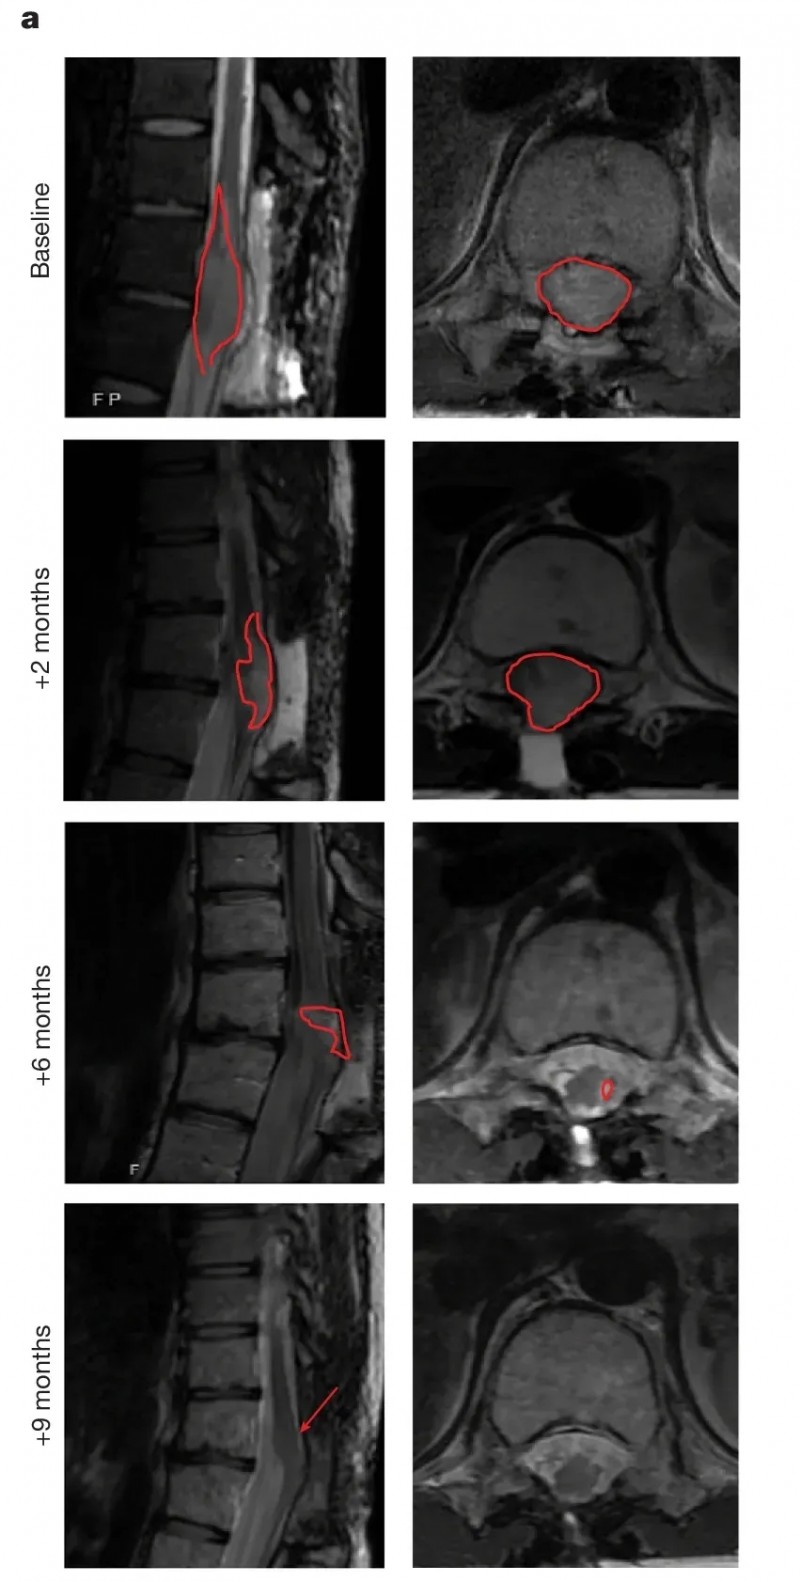

006号患者(sDMG):7个月肿瘤缩小91%,截瘫症状缓解

该患者确诊脊髓弥漫性中线神经胶质瘤(sDMG)时,已处于临床与放射学肿瘤进展期。首次输注GD2-CAR-T细胞后7个月,肿瘤体积显著缩小91%。治疗前,T11/12水平脊髓肿瘤弥漫性浸润,脊髓扩张填满椎管,无周围脑脊液(CSF);治疗后脊髓逐渐恢复正常大小,T2信号异常基本消失(详见下图)。

在临床症状方面,患者入组时伴有严重截瘫、神经性疼痛、肠道/膀胱功能障碍;在肿瘤缩小90%以上的最佳反应期,疼痛明显缓解,下肢功能改善,可借助拐杖行走。

▲图源“nature”,版权归原作者所有,如无意中侵犯了知识产权,请联系我们删除